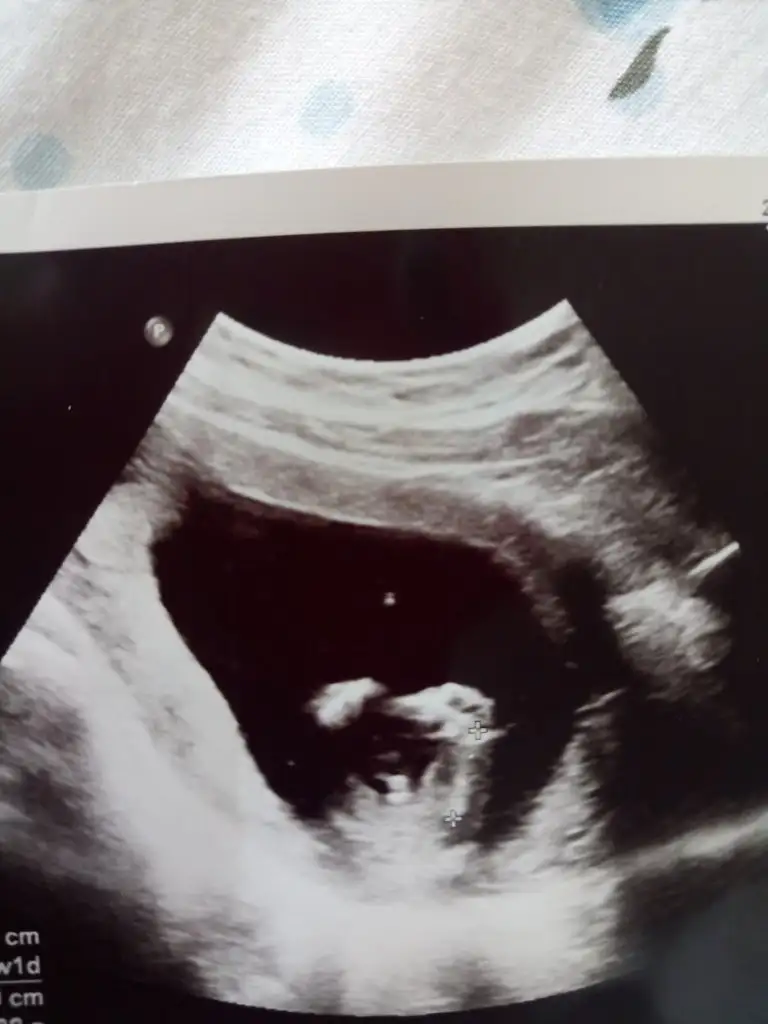

Cinsiyetini öğrendiğimiz gün oglumun ultrason fotoları alnı çıkıntılı mı anlayamadım tam ama bacak arasındaki çıkıntı ben burdayim demiş

ay bizde böyle görmüştük büllüğü tabak gibi meydandaydı